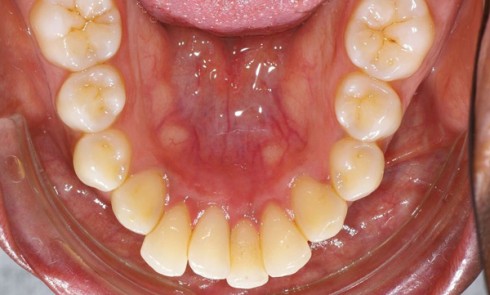

Présentation du cas Il s’agit d’un patient adulte de 28 ans (fig. 1) présentant une classe I, une dysharmonie dento-maxillaire (DDM),...